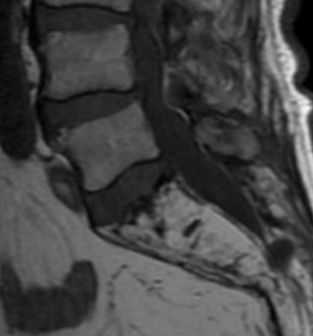

МРТ позвоночника. Т1-взвешенная сагиттальная МРТ пояснично-крестцового отдела. Замещение костного мозга крестца жиром при болезни Пэджета.